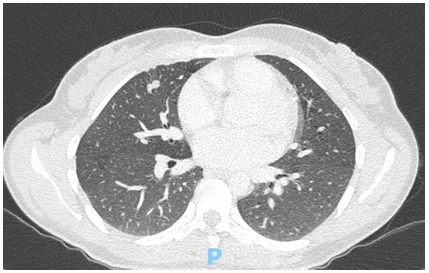

Al mes de iniciado el tratamiento se realiza primer control con subunidad BHCG con un resultado de 202 mU/ml y al finalizar el mismo se encuentra un resultado de 3 mU/ml, una vez alcanzado este valor se realiza el mantenimiento con mismo esquema quimioterápico durante 1 mes, y se repite el dosaje de BHCG con un valor de 1 mU/ml. Además se solicitaron nuevos estudios por imágenes en base a las recomendaciones: TC tórax(Imagen 4), abdomen y pelvis(Imagen 5), y RMN de cerebro(Imagen 6) (no pudiéndose solicitar PET-TC debido a falta de cobertura por la obra social), en los mismos se encontró marcada disminución de tamaño de las imágenes nodulares en ambos campos pulmonares, imágenes focales hepáticas hipovasculares, correspondientes a imágenes secuelares e hipodensidad subcapsular esplénica de aspecto isquémico secuelar. En la RMN se informa alteración de la señal temporo-occipital izquierda de aspecto secuelar, probablemente en relación a restos de hemosiderina.

Imagen 4. TC tórax post-tto